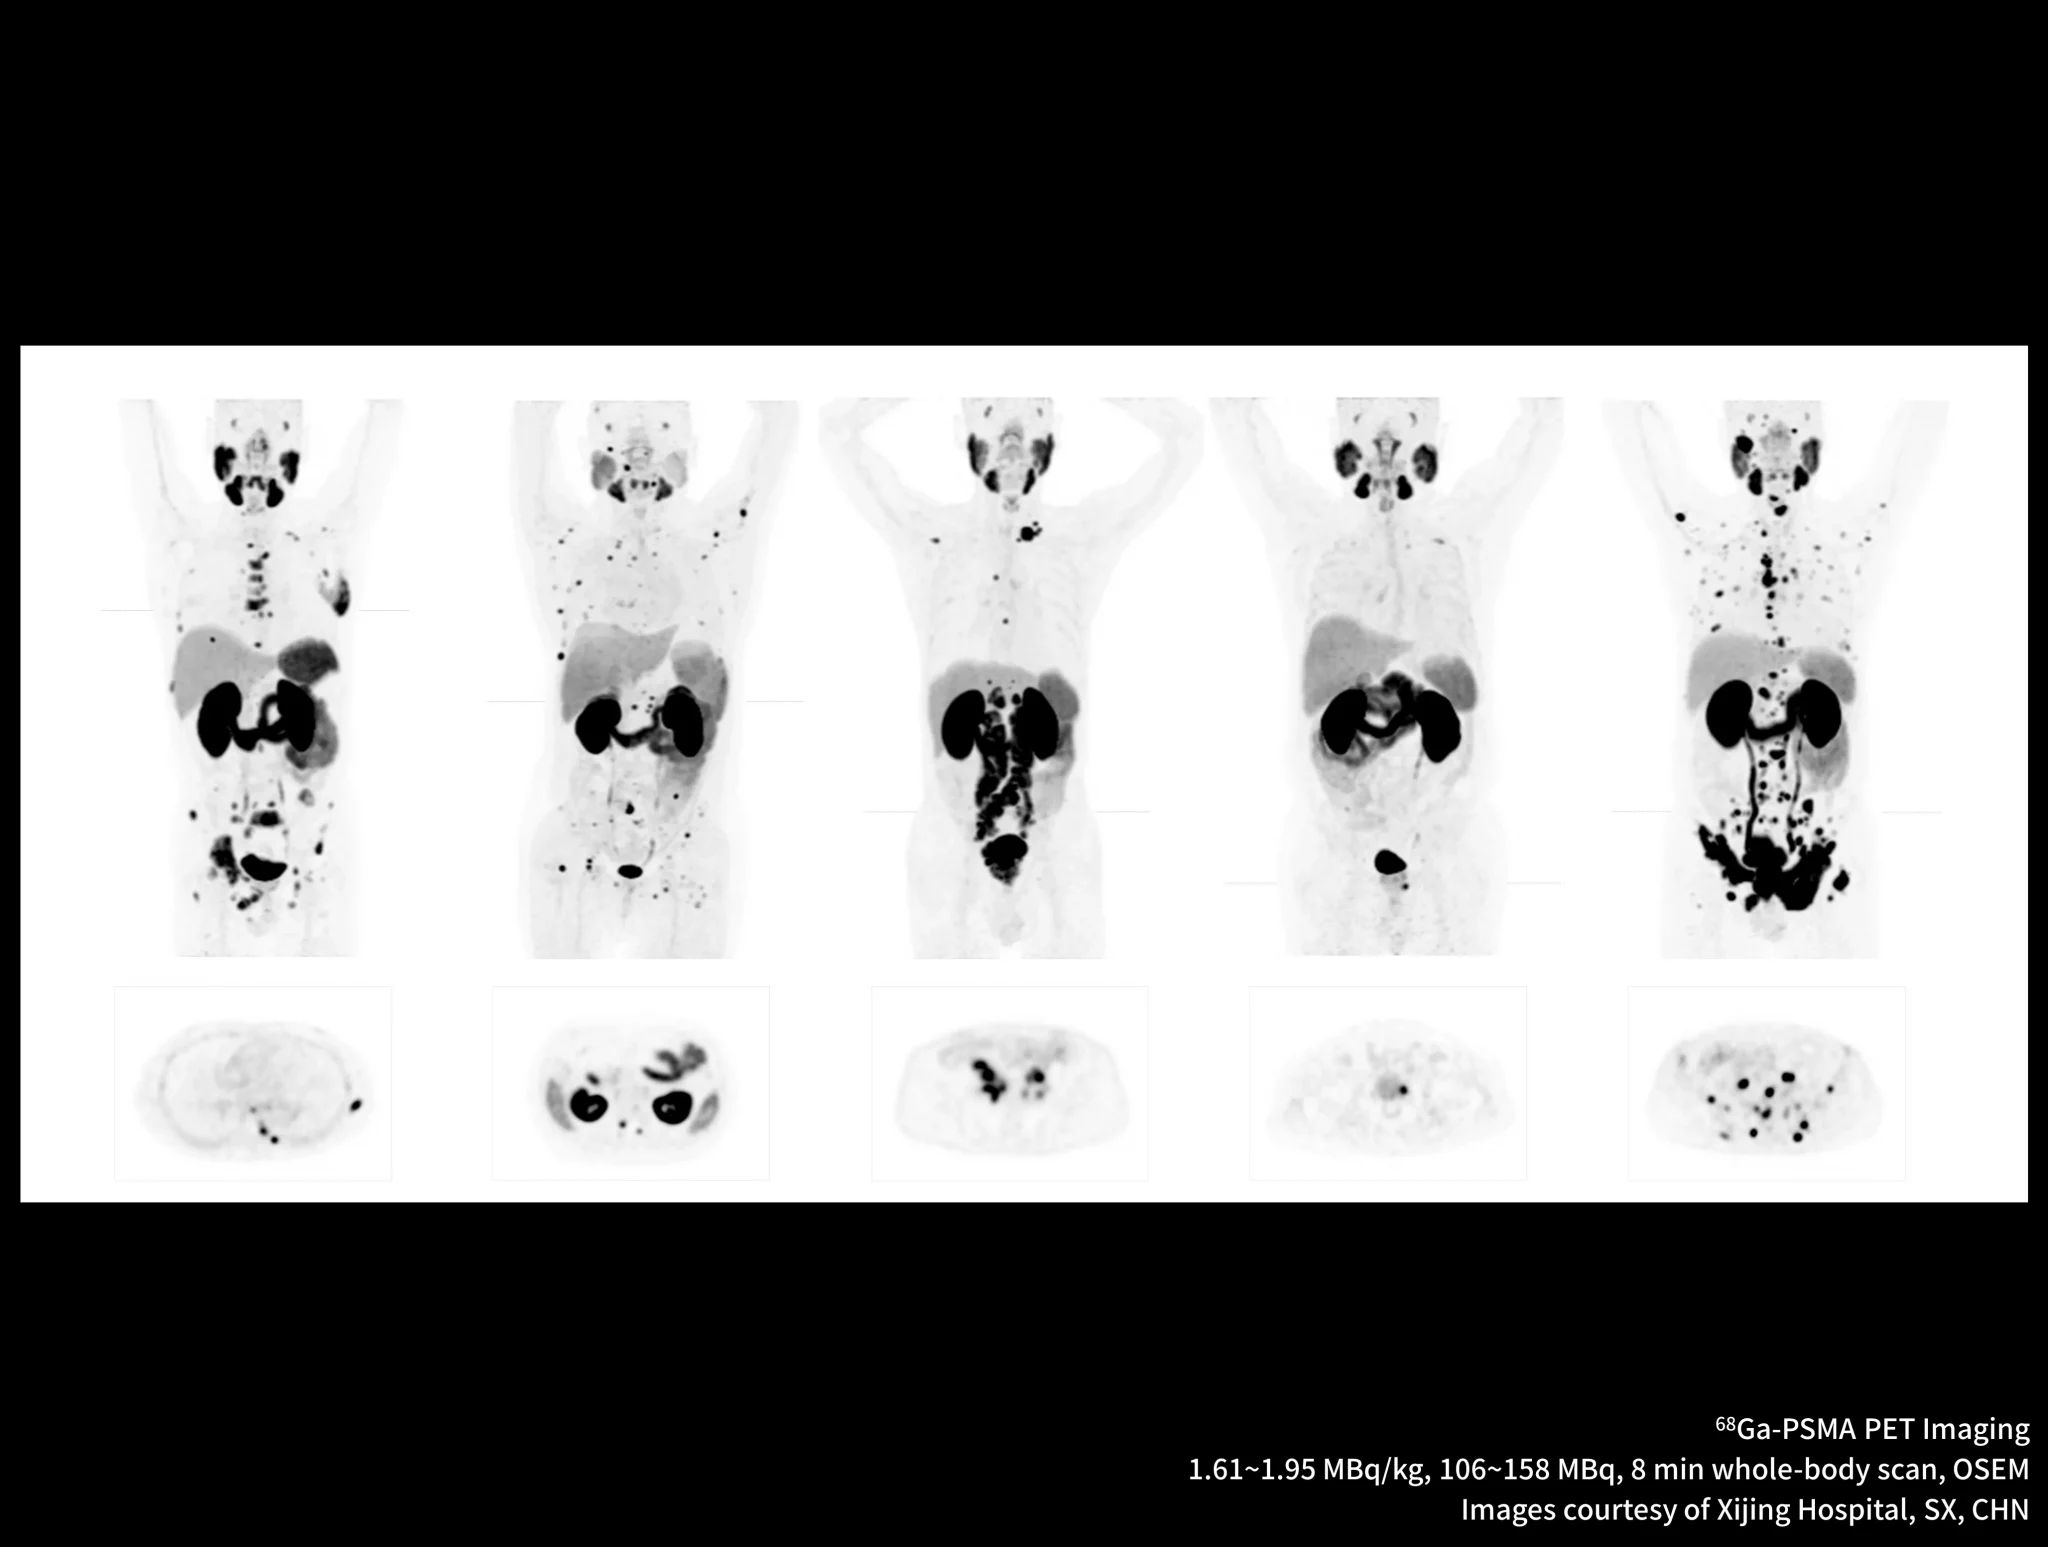

New-Tracer Imaging

Click on different tracers to see the images.